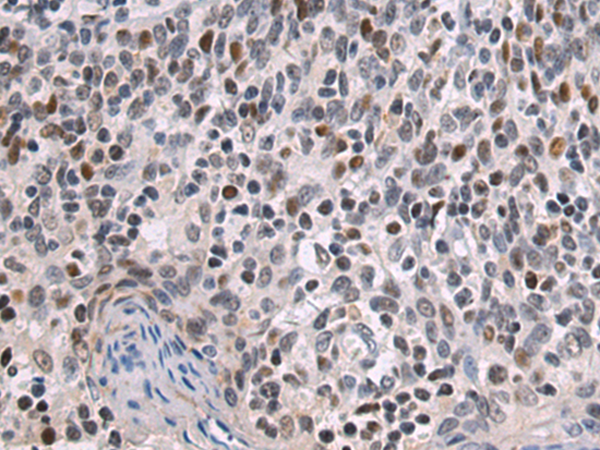

分类: 科研抗体货号: P10627别名: ndrp; BRWD2; DIDOD; WDR11; DCAF14; CHUJANS应用: IHC反应种属: Human, Mouse

鄂公网安备42018502007531号